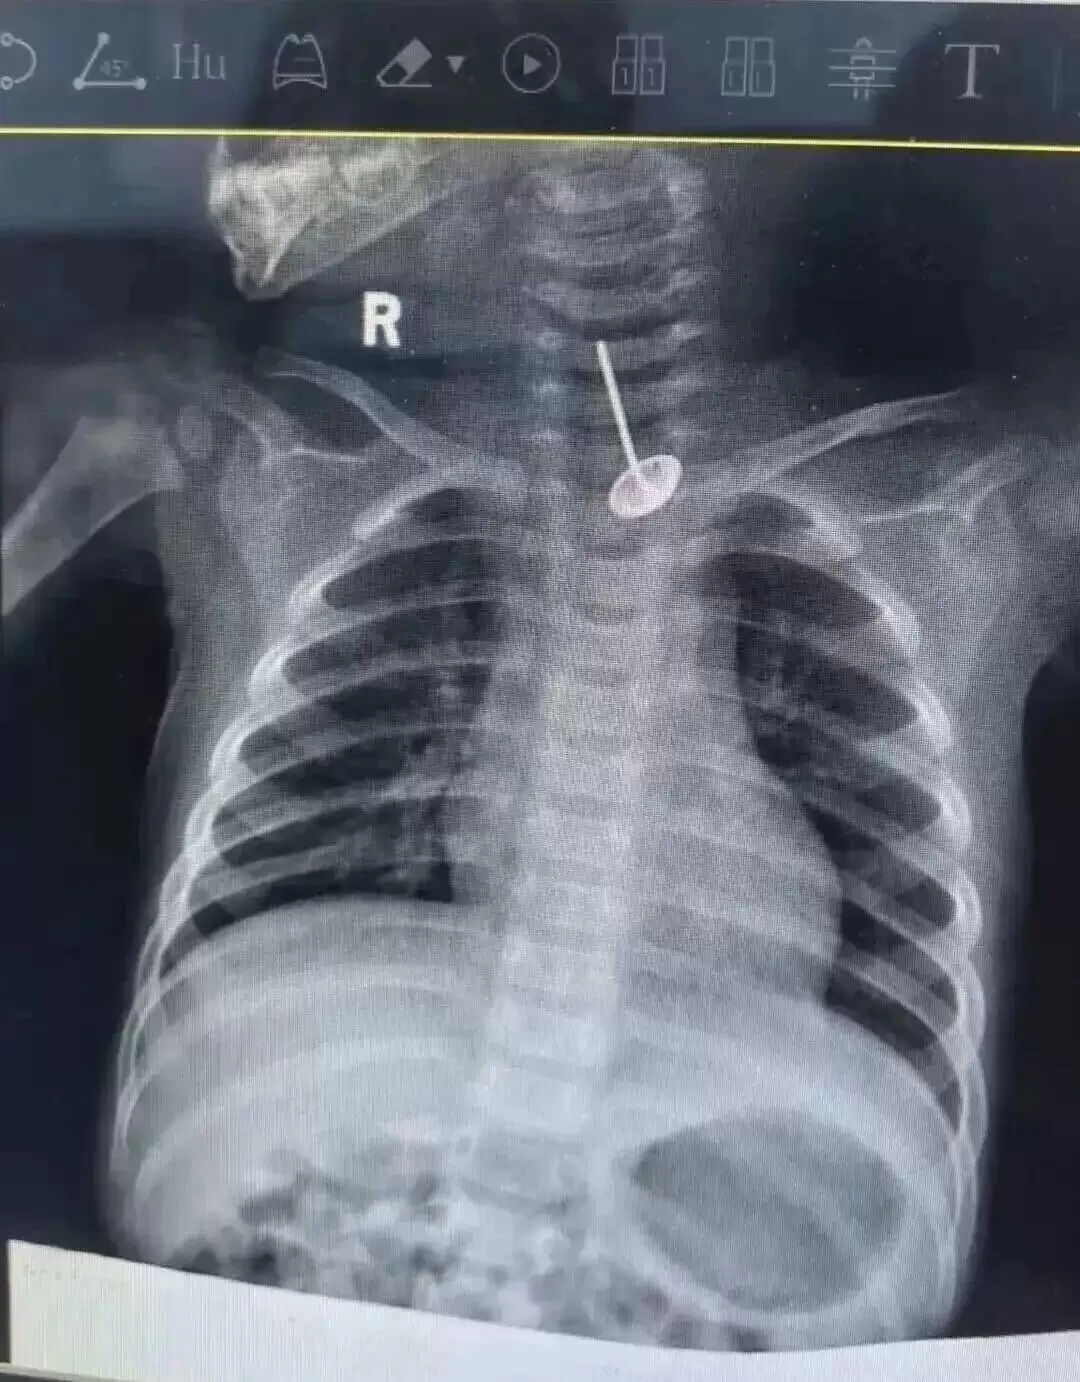

然而,就在术前完善胸片检查时,医护人员发现了更加惊险的一幕:小西的食管内竟卡着一个形似图钉的尖锐金属异物。胸部增强CT检查显示,该异物长达3厘米,已刺破食管壁,尖端紧邻主动脉弓,一旦刺穿大血管,瞬间便会引发大出血,生命危在旦夕。情况紧急,口腔颌面外科立即联系小儿外科协助救治。

d1.jpg ▲CT显示孩子食管内卡着异物